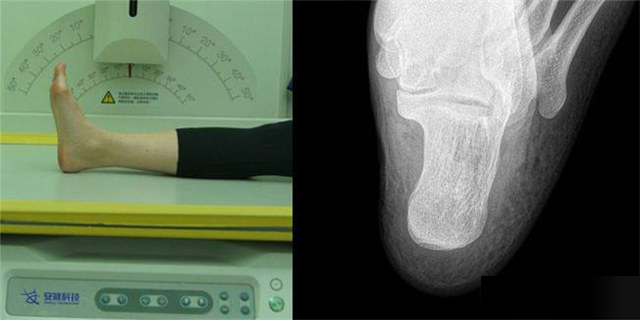

下肢:脛腓骨、踝、足脛腓骨長骨檢查需要包括--側(cè)的關(guān)節(jié)踝關(guān)節(jié)常規(guī)正+外側(cè)位,特殊時可選內(nèi)斜位足常規(guī)前后正位+內(nèi)斜位,外傷鑒定等情況,需要負重的水平側(cè)位(包括足尖和足跟)跟骨側(cè)位+軸位